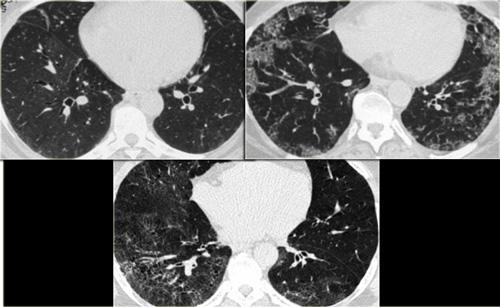

Bên trái là hai trường hợp NSIP.

Lưu ý sự kết hợp đa dạng giữa GGO và xơ hóa (giãn phế quản do co kéo), nhưng không có hình ảnh tổ ong.

Trong các hình ảnh bên trái, bạn có thể thấy lại phổ các dấu hiệu gặp trong NSIP.

Cả ba bệnh nhân đều mắc bệnh mô liên kết và tất cả các trường hợp đều được xác nhận bằng sinh thiết.

Trường hợp đầu tiên (trên bên trái) cho thấy GGO rất tinh tế.

Lưu ý sự khác biệt về tỷ trọng giữa không khí trong phế quản và nhu mô phổi xung quanh (dấu hiệu phế quản tối).

Trường hợp thứ hai (trên bên phải) là ví dụ rõ ràng hơn về GGO với các đậm độ dạng lưới mịn chồng lên do dày vách tiểu thùy.

Hình ảnh cuối cùng cũng cho thấy GGO với dạng lưới mịn.

Lưu ý sự vắng mặt của hình ảnh tổ ong trong cả ba trường hợp, loại trừ UIP là chẩn đoán.